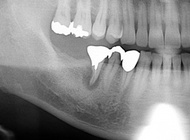

三鷹市、ファミリー歯科医院、院長の佐野真弘です。 先日、右下欠損部に対してインプラント処置が行われました。 左の写真から右の写真に至るまでは、ある程度の期間かけていろいろなことをやっておりますが、悪い歯を放置して骨が吸収…